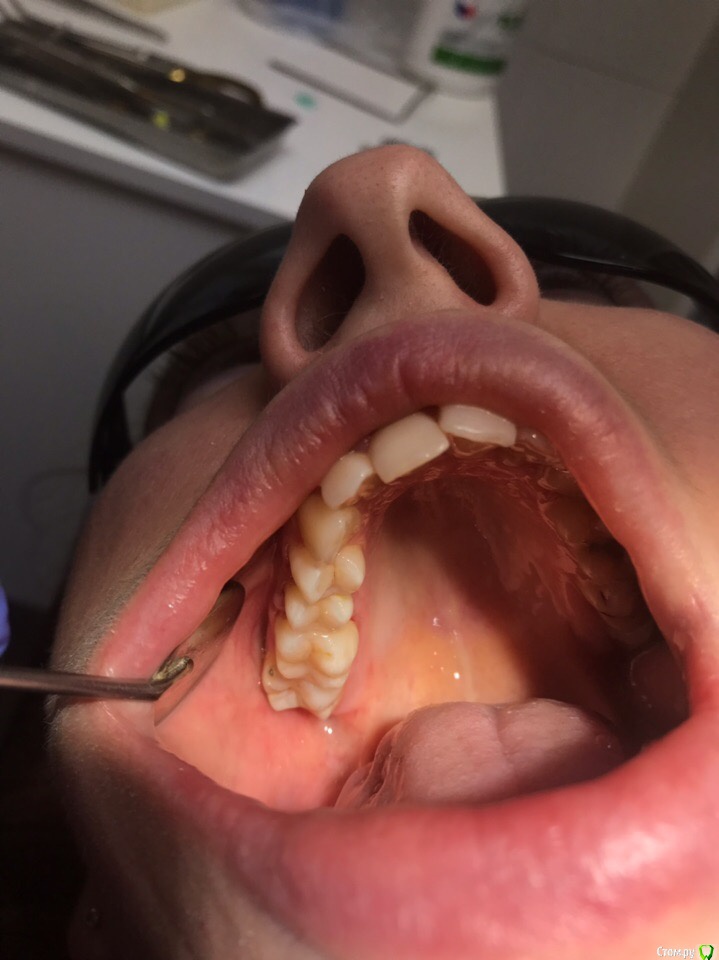

1586Doc Опубликовано 30 марта, 2019 Автор Поделиться Опубликовано 30 марта, 2019 (изменено) Еще немного работы45 зуб эндо и пломба и 46 зуб эндо и пломба на снимке справа Изменено 30 марта, 2019 пользователем 1586Doc Ссылка на комментарий